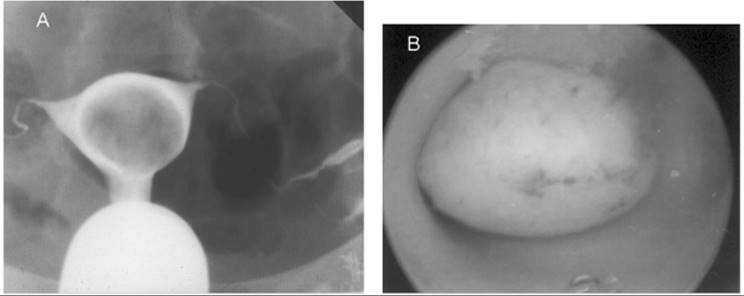

The closer the fibroid is to the endometrial cavity, the greater the likelihood and severity of dysmenorrhea and menorrhagia. Additionally, distortion of the endometrial cavity increases the probability of difficulty in achieving and maintaining a pregnancy. Hysterosalpingography often is undertaken if infertility is present concurrently, because this technique can identify intracavitary tumors or an otherwise normal endometrial cavity enlarged by stretching of the normal myometrium around leiomyomata (Fig. 49.3). This radiographic technique has the added advantage of determining tubal patency. Removal of leiomyomata will not improve the likelihood of conception unless an enlarged endometrial cavity, an irregular endometrial contour, or an intracavitary defect is present. Increasingly, office hysteroscopy is being used when tubal patency is not an issue, because this technique allows clear differentiation between leiomyomata and other intracavitary pathology, such as endometrial adhesions, uterine septae, and endometrial polyps.

FIG. 49.3. An intracavitary leiomyoma. A: A hysterosalpingogram using a water-soluble contrast medium demonstrates a large, smooth filling defect within the endometrial cavity resulting from an intracavitary fibroid. The mass effect on the study is nonspecific, and only direct visualization can confirm that it is caused by a fibroid. B: The hysteroscopic view of this intracavitary leiomyoma.